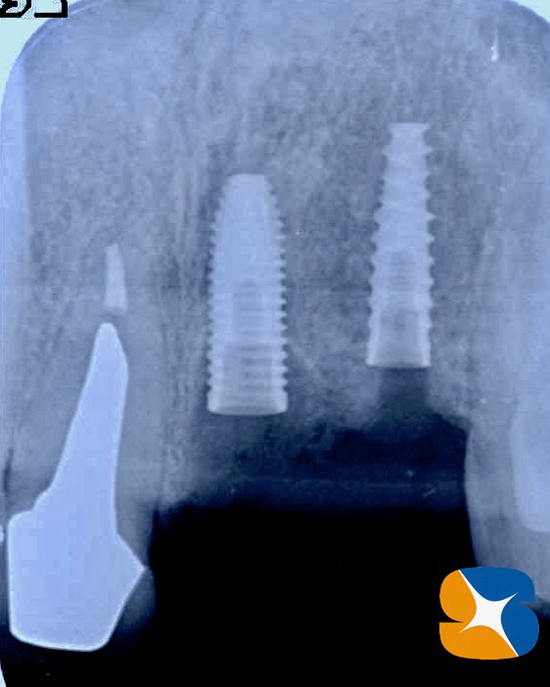

(2)次にインプラント部を一般的なレントゲンでチェックしましたが、特に問題となるような所見はありませんでしたが…。

歯科用のCT画像で確認すると確かに薄い骨幅の骨の断面から、インプラントが突き抜けていることが判明いたしました。

(1)割れた根と(2)骨から突き抜けたインプラントを確認することが出来ました。

使用インプラント:(左)ノーベルバイオケア社製のパラレルCC 直径3.75㎜、長さ13㎜。

(右)アクティブ 直径3.0㎜、長さ13㎜。